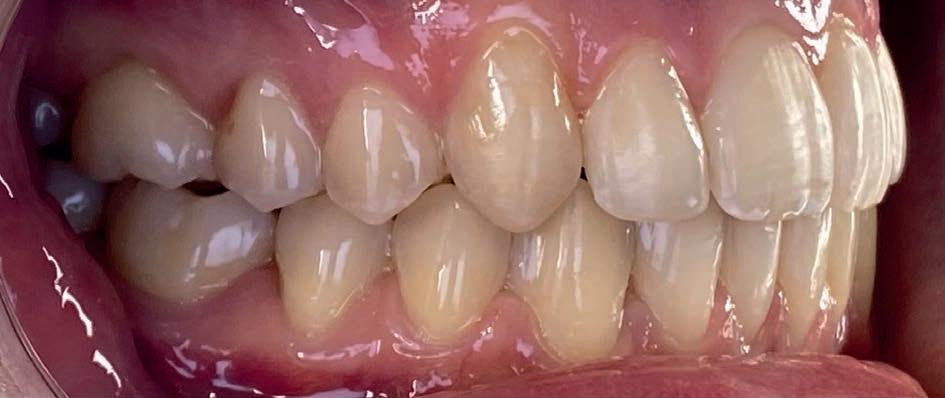

Casus: Blix – Ruimte creëren zonder extracties met D-gainer en Damon Ultima Blix (10 jaar) presenteerde zich met een klasse II-occlusie, smalle boven- en onderkaak en ruimtegebrek voor de doorbraak van de hoektanden en premolaren. Hoewel haar gezicht in balans was, zou zonder behandeling het gebrek aan ruimte toenemen en de diepe beet verder verergeren.

Behandeling in twee fasen

1. D-gainer & verbreding

Om extracties te voorkomen, werd gestart met een D-gainer. Dit is een methode met slotjes en veertjes waarmee de molaren gecontroleerd naar achteren worden verplaatst. Tegelijkertijd werd de tandboog verbreed – zonder buitenboordbeugel.

• Doel: ruimte creëren voor de hoektanden (13/23) zonder premolaren te verwijderen

• Duur: ongeveer 6 maanden

2. Vaste beugel (Damon Ultima)

Na voldoende ruimte werd gestart met de volledige vaste beugel in boven- en onderkaak. Hiermee werden de tandbogen uitgevlakt, de scheefstand gecorrigeerd en de tandbogen verbreed – met behoud van het natuurlijke profiel.

Resultaat

• Klasse I-occlusie

• Harmonieuze lachlijn en verbrede tandbogen

• Geen extracties

• Profiel en gezichtsbalans behouden

Retentie: Vaste spalk boven én onder, aangevuld met een nachtbeugel

“Door ruimte te creëren met een D-gainer in plaats van tanden te trekken, blijft het profiel natuurlijk en ontstaat een bredere, stabiele tandboog.”